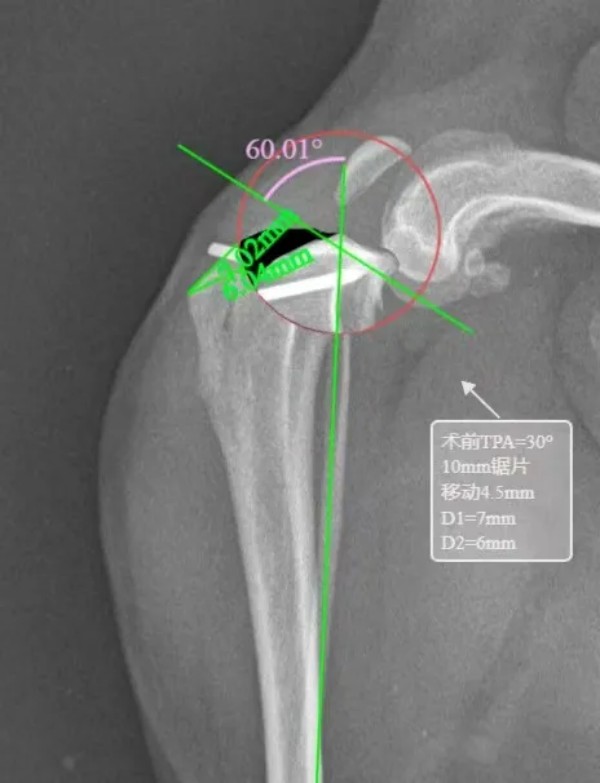

选用2.0型号宠多助TPLO-L骨板,术前TPA=30角°,应用10mm锯片,移动距离4.5mm

术前规划